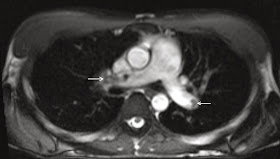

Series 5: Axial T2 navigator-triggered

We have found T2 TSE BLADE/PROPELLER to be qualitatively comparable to, if not favored over, conventional T2 TSE acquisitions, particularly given the reduced sensitivity to cardiac motion and increased sharpness of the major tissue interfaces. Fat saturation is routinely employed for this series. In addition to lesion characterization, this sequence is highly useful for the evaluation of lymphadenopathy and regional bone marrow signal.